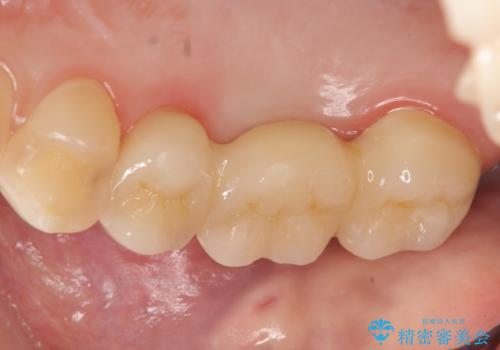

その後歯茎や骨の回復を待ち、オールセラミッククラウンのブリッジによる補綴を行いました。

今回用いたオールセラミッククラウンはジルコニアフレームという白い素材の上にセラミックを盛っているため、審美性が非常に高いのが特徴です。

また、ジルコニアは人工ダイヤモンドの材料にも使われているほど高い強度を持っており、そのためオールセラミッククラウンは審美性だけでなく、奥歯やブリッジの補綴も可能とするクラウンです。